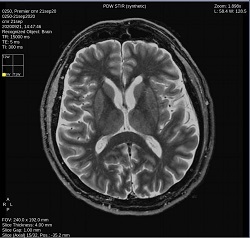

- By default, a 6-viewport display is launched with 6 unique MAGiC images.

Click PDW STIR to change the image contrast to synthetic PDW STIR-weighted.